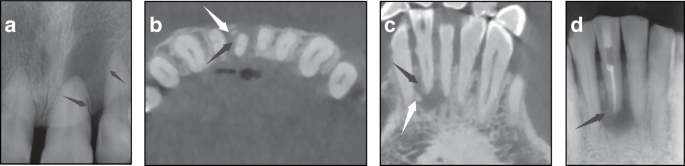

Cemental tear is a rare and indetectable condition unless obvious clinical signs present with the involvement of surrounding periodontal and periapical tissues. Due to its clinical manifestations similar to common dental issues, such as vertical root fracture, primary endodontic diseases, and periodontal diseases, as well as the low awareness of cemental tear for clinicians, misdiagnosis often occurs. The critical principle for cemental tear treatment is to remove torn fragments, and overlooking fragments leads to futile therapy, which could deteriorate the conditions of the affected teeth. Therefore, accurate diagnosis and subsequent appropriate interventions are vital for managing cemental tear. Novel diagnostic tools, including cone-beam computed tomography (CBCT), microscopes, and enamel matrix derivatives, have improved early detection and management, enhancing tooth retention. The implementation of standardized diagnostic criteria and treatment protocols, combined with improved clinical awareness among dental professionals, serves to mitigate risks of diagnostic errors and suboptimal therapeutic interventions. This expert consensus reviewed the epidemiology, pathogenesis, potential predisposing factors, clinical manifestations, diagnosis, differential diagnosis, treatment, and prognosis of cemental tear, aiming to provide a clinical guideline and facilitate clinicians to have a better understanding of cemental tear.